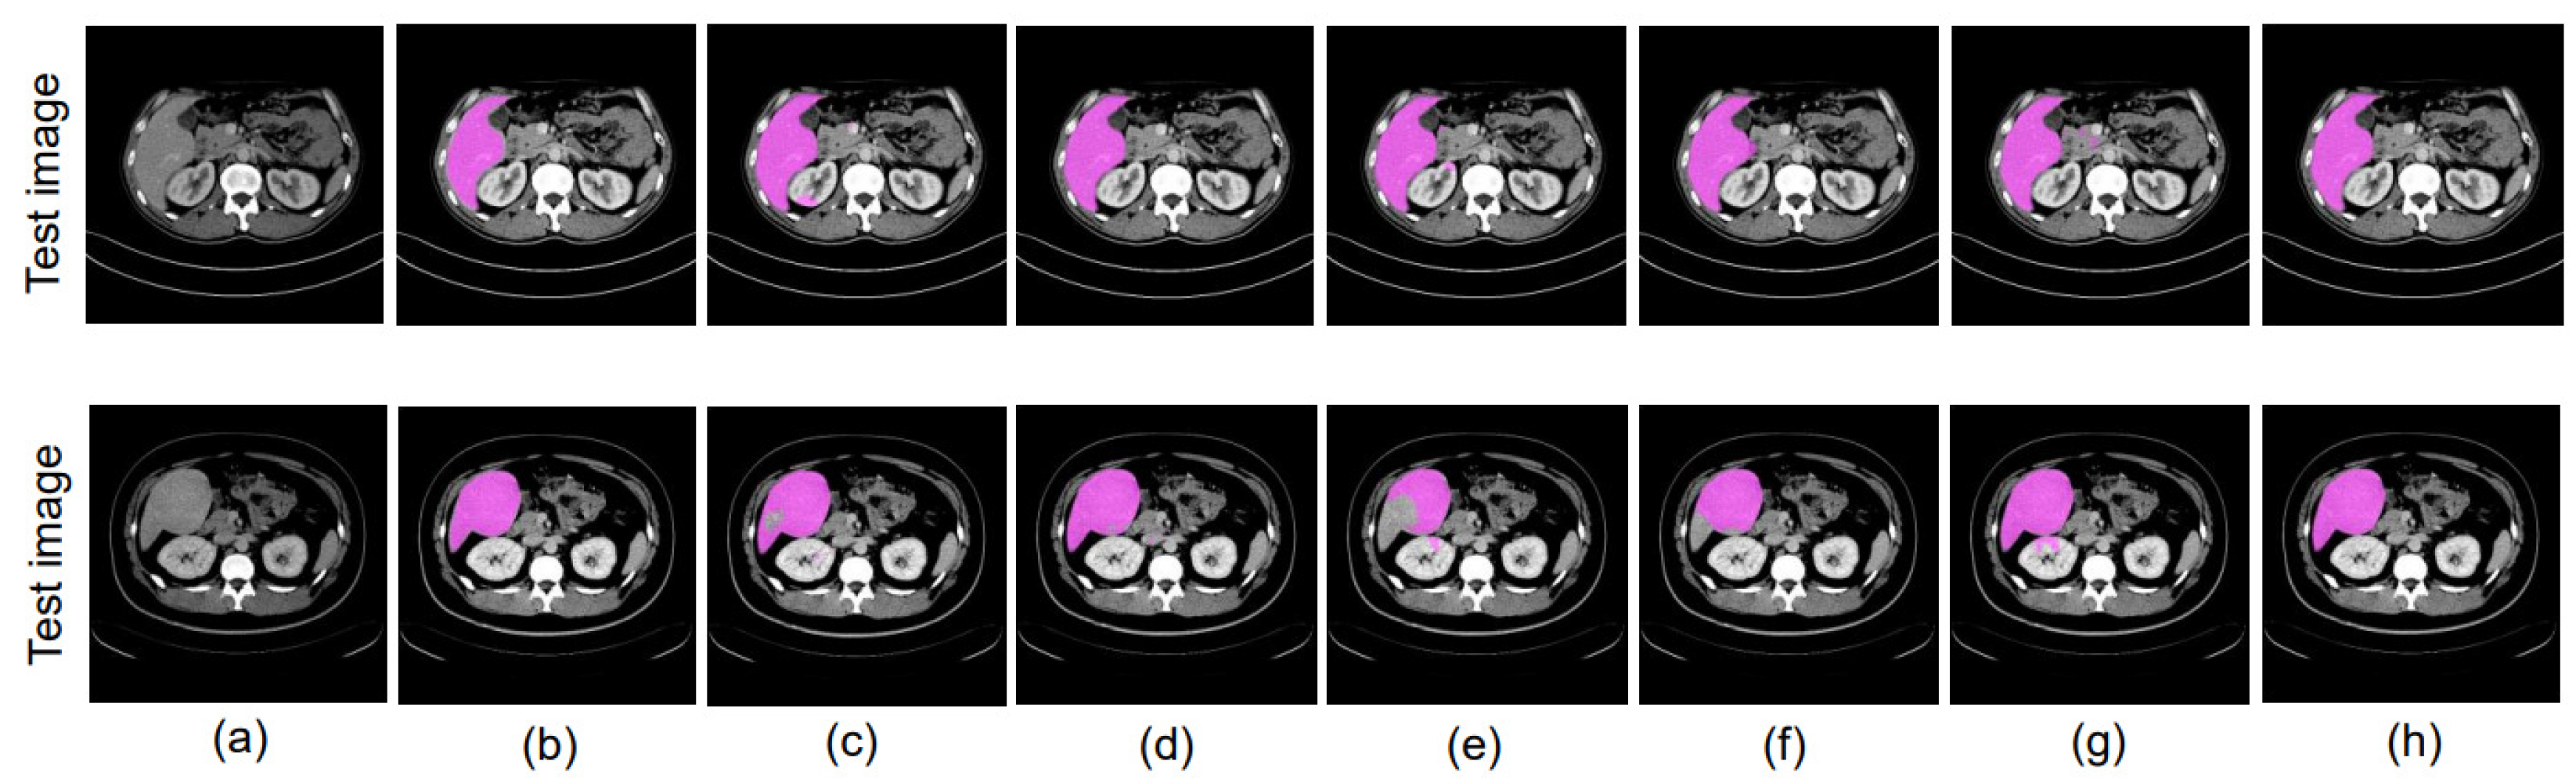

4.8.1. Different Datacenter and Same Phase